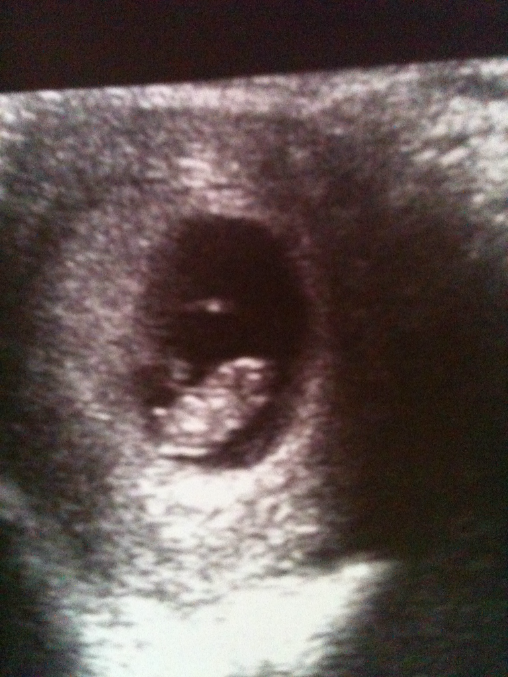

Была на УЗИ сегодня!!!

Все хорошо, очень боялась, потому что кровило почему-то... обнаружили гематому, но сказала что ничего страшного, что беспокоить больше не будет... КТР 22 мм, соответствует 9 неделям и 4 дням) такой пупсик, сердечко бьется, дали послушать)))фото под кат

Справа голова))) даже пуповину видно)) и ПУЗЕНЬ)))) даже врач посмеялась-говорит пузатик)))